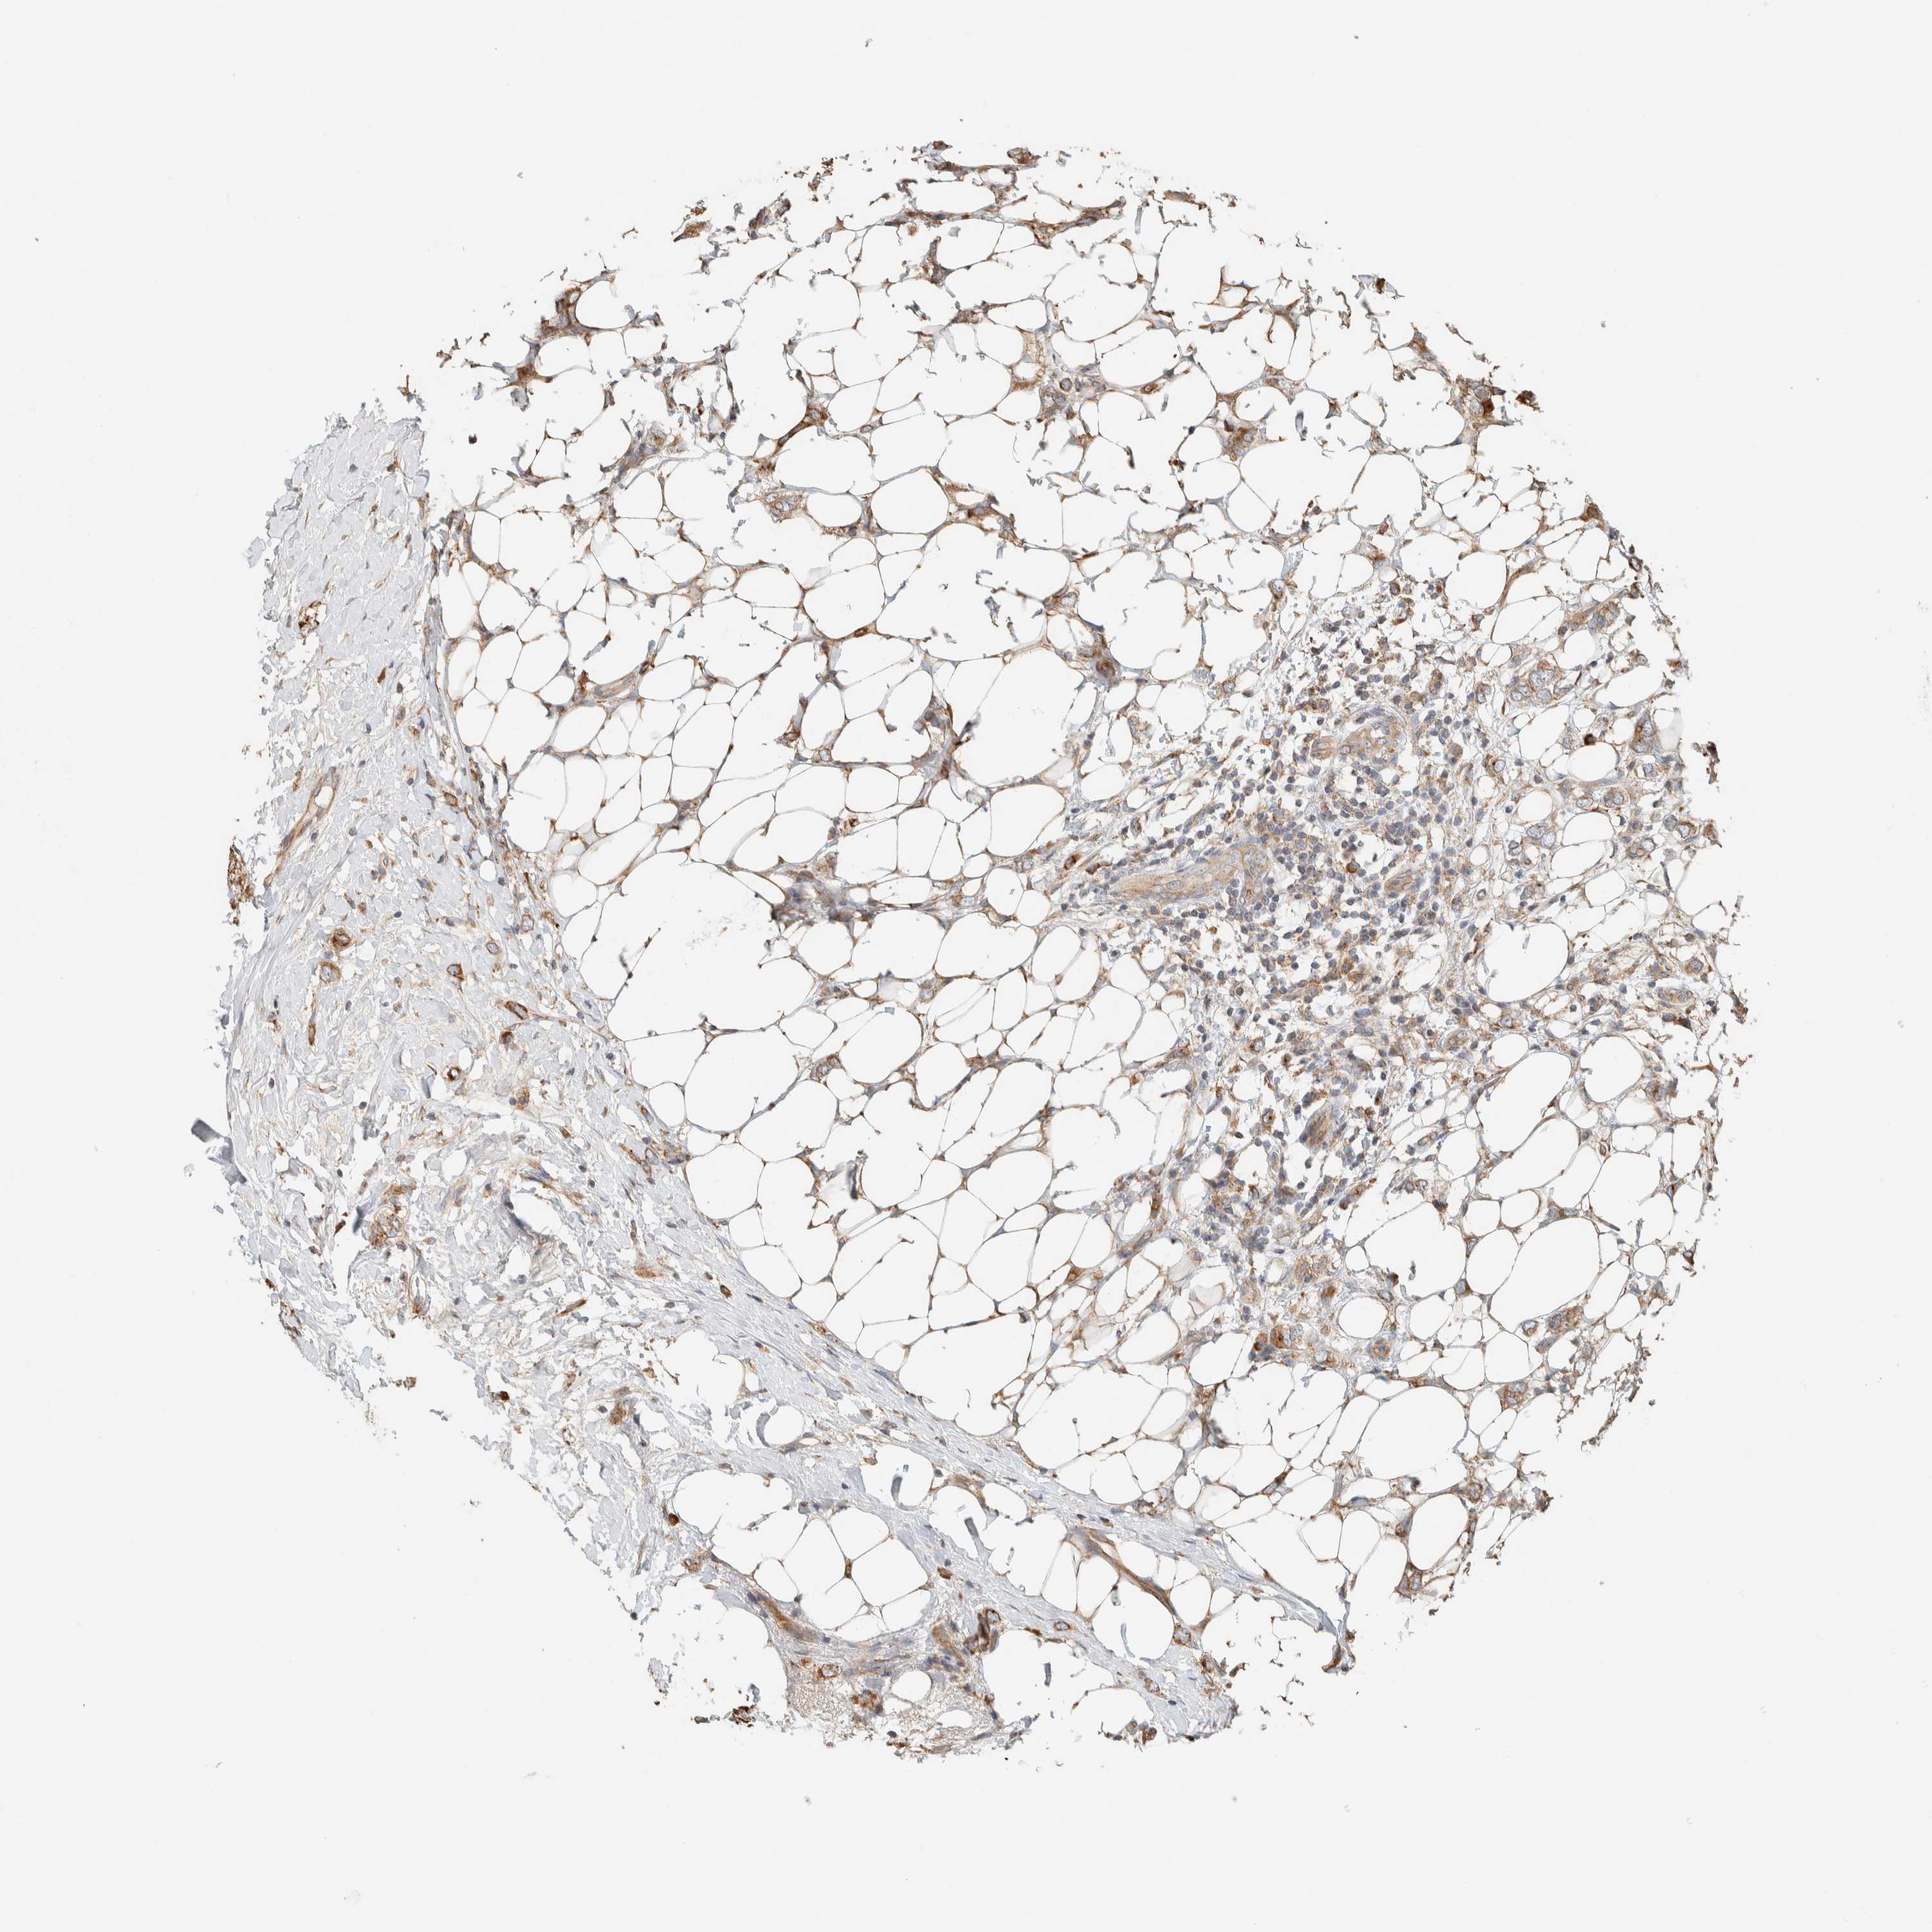

CANCER BREAST CANCER Show tissue menu

BRCA TCGA BRCA VALIDATION PROTEIN EXPRESSION